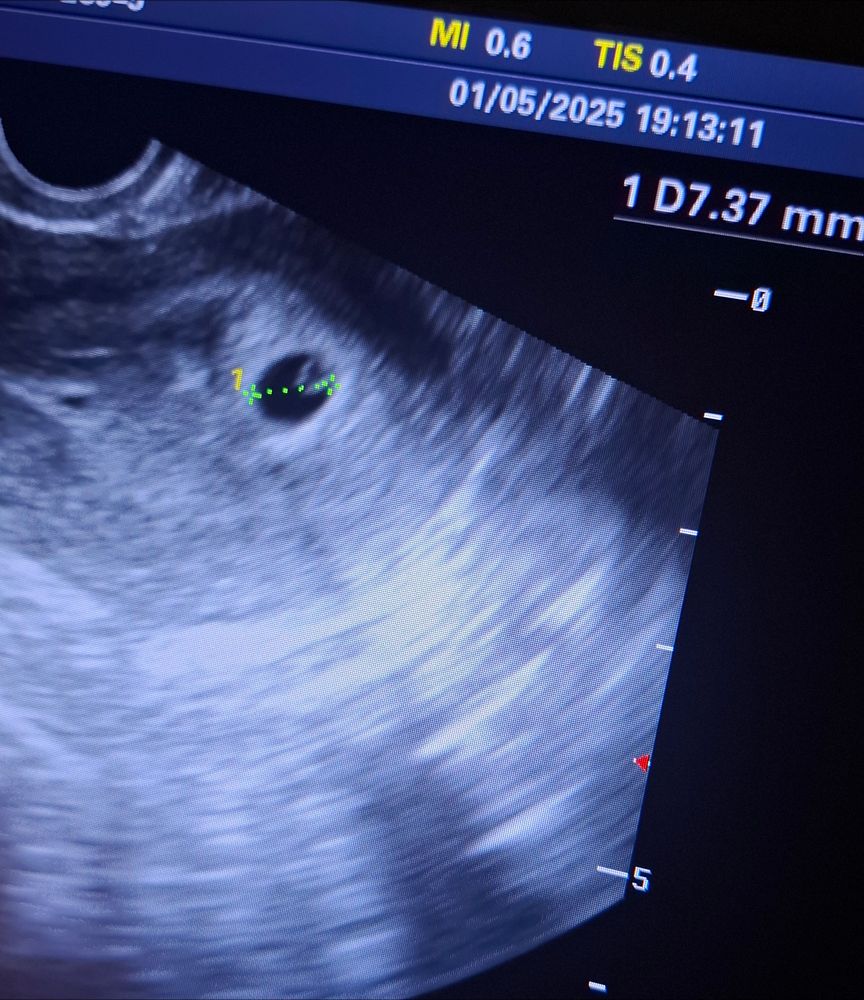

На панике вызвала скорую, меня осмотрели, сделали узи. Первое узи делала 24.12, плодное яйцо было 2 мм. Сегодня уже 7,37 мм, желточный мешочек есть, но эмбриона нет. Надеюсь, это нормально..

Выписали дюфастон и транексам, надеюсь, что они помогут сохранить малыша 🥺🙏